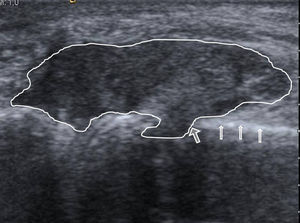

En la ecografía no se evidenció derrame, pero sí una lesión de las partes blandas, parcialmente definida, y de ecoestructura heterogénea, con áreas hiperecoicas. La tumoración estaba en contacto con la cortical ósea del metacarpiano, que se mantenía intacta, salvo en una zona donde se objetivó una franca erosión, con la lesión de partes blandas proyectándose dentro de la cavidad medular (fig. 1). Ante los hallazgos de la ecografía, se analizó la radiografía, que confirmó el aumento de las partes blandas periarticulares, con muy alta densidad, acompañado de erosión en la cabeza del metacarpiano, que como dato característico tenía un margen escleroso (fig. 2). Estos hallazgos ecográficos y radiográficos indicaron un tofo gotoso periarticular con erosión ósea asociada. La punción ecoguiada del posible tofo mostró un material denso blanquecino, que al microscopio de luz polarizada puso de manifiesto los cristales de urato monosódico (fig. 3).